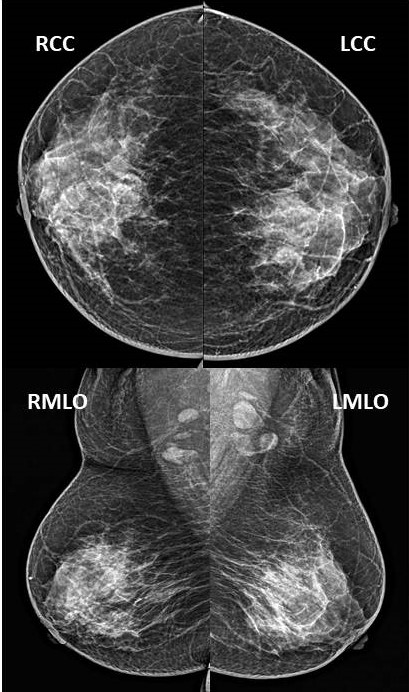

Full-field digital mammography (FFDM), bilateral CC and MLO view showed extremely dense breast tissue with no obvious abnormality [Figure 1]. Ultrasound (US) of the breast showed non-specific findings with non-circumscribed mixed echogenic area in the region of palpable lump at 12 o’clock, and a lymph node with eccentric cortical thickening in right axilla [Figure 2]. Subsequent US guided right axillary lymph node FNAC showed reactive hyperplasia. She was followed up after 3 months with persistence of her clinical symptom which was stable. This time she was evaluated with contrast enhanced mammography (CEM) which revealed heterogeneous non-mass enhancement in segmental distribution measuring 56 x 60mm in the central portion of right breast [Figure 3]. Pre-operative dynamic post contrast breast MRI showed nodular and clustered ring non-mass enhancement [Figure 4] in the similar distribution as in CEM. No other abnormality was seen in rest of the right breast and contralateral breast. US guided core needle biopsy of the right breast mass and the final histopathology of the mastectomy specimen yielded ductal carcinoma in situ (DCIS), solid type nuclear grade III without invasion [Figure 5]. Sentinel node biopsy was negative for malignancy.